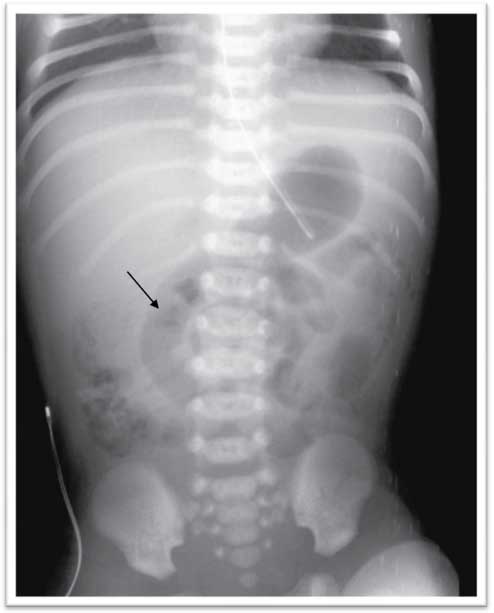

A female infant was born at 36 weeks of gestation to a 30-year-old woman by spontaneous vaginal delivery. The mother was positive for Streptococcus group B and received adequate intrapartum chemoprophylaxis with ampicillin. She had no signs of chorioamnionitis. The APGAR scores were 9, 10 and 10 at 1, 5 and 10 min, respectively. The birth weight was 2760 g. The baby was admitted at 2 h of life due to hypoglycemia (35 mg/dL) and poor feeding. Intravenous fluids containing glucose at 4.5 mg/kg per minute were initiated, with an increase in glucose levels to more than 60 mg/dL. She presented no subsequent episodes of hypoglycemia and started enteral feeding with formula. Whole blood examination and C reactive protein (CRP) on admission were normal. On the second day of life, the infant appeared to be uncomfortable and presented with bloody stools and bile-stained gastric aspirate. Whole blood analysis, CRP and routine coagulation tests were repeated, revealing no abnormalities. Abdominal X-ray showed signs of suspected obstruction, and the abdominal ultrasound revealed a small quantity of free abdominal fluid. Antibiotics (ampicillin and gentamicin) were started. The infant continued to pass bloody stools, bile-stained and bloody gastric aspirate, and abdominal distension. On day 3, she presented with leukopenia of 2700/mm3 (neutrophils 50%) and platelet count of 144,000/mm3. CRP increased to a maximum of 63 mg/L. At this point metronidazole was added. Abdominal ultrasound revealed an increase in free abdominal fluid compared with the previous examination; the mesenteric vein/mesenteric artery ratio was preserved. Abdominal X-ray showed a fixed loop, outlining a whirlpool sign, and no signs of intestinal pneumatosis (Figure 1). A diagnostic laparoscopy was performed. A 5-mm supraumbilical port was inserted. This procedure showed good intestinal vascularization, slight delegate distension and normal colon. Then 3-mm instruments were inserted under direct vision via stab incisions, enabling identification of generalized peritonitis secondary to inflammatory process in the right iliac fossa, likely to be appendicitis. Laparoscopic appendectomy was performed (Figure 2). There were no intraoperative complications, and the infant had a good postoperative recovery. She received regular paracetamol for pain relief and did not require morphine. The patient started feeding 3 days after surgery and received full feeds by the fifth postoperative day. She was treated with antibiotics for 10 days and discharged at day 9 postoperatively.

Abdominal X-ray showing a fixed loop and outlining a whirlpool sign (arrow).